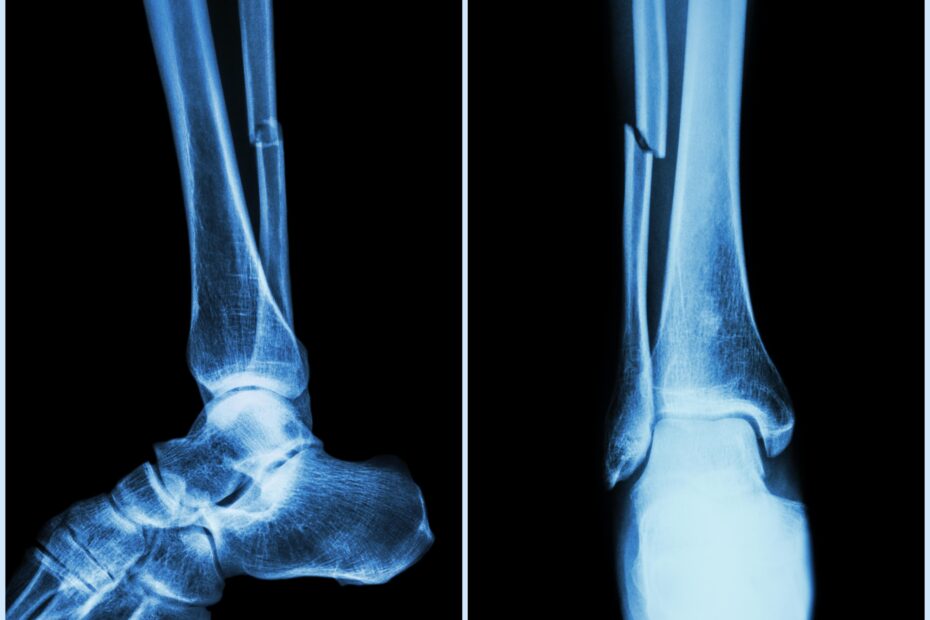

Fracturi vindecate în câteva minute: un lipici pentru oase, soluția găsită de cercetătorii chinezi

Cercetătorii chinezi susţin că au dezvoltat un adeziv osos care poate fi folosit pentru a trata fracturile şi fragmentele osoase zdrobite, printr-o procedură care durează… Citește mai mult »Fracturi vindecate în câteva minute: un lipici pentru oase, soluția găsită de cercetătorii chinezi